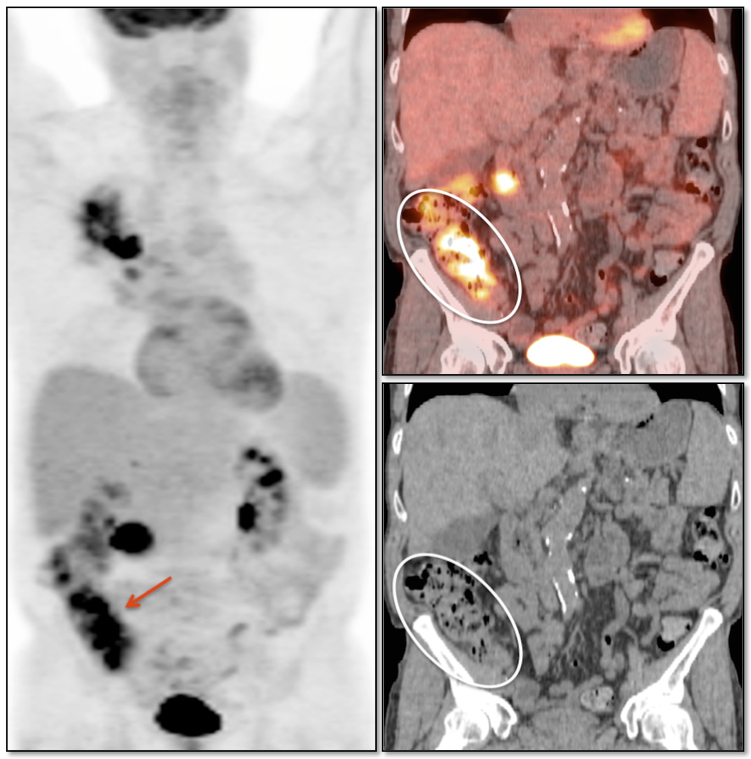

• Restaging known recurrence, especially if surgery is contemplated.

• Distinguishing recurrence from post-therapeutic inflammation/scarring.

The most common sites of metastatic disease include the lymph nodes (regional & distant), liver, lung, peritoneal cavity, bones, brain and adrenal glands.